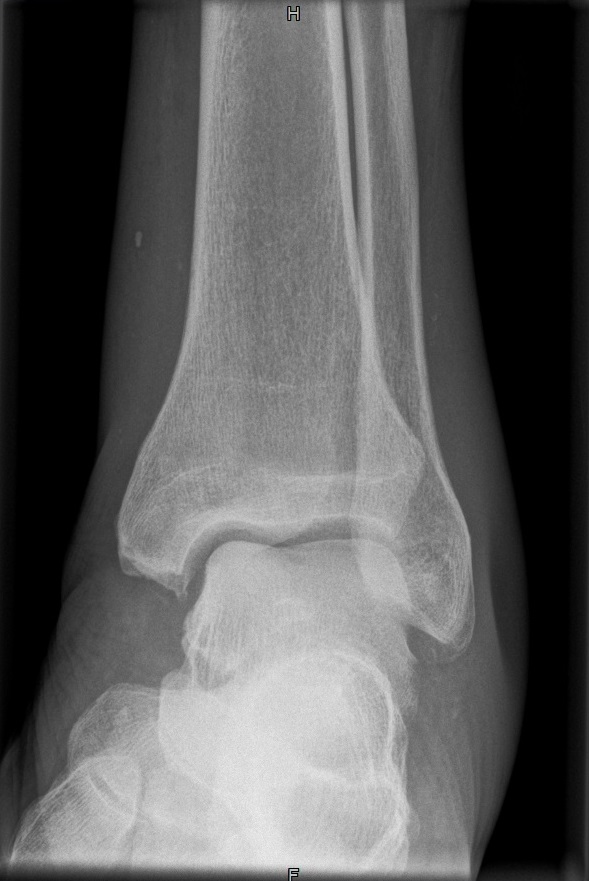

OSG seitlich

132_4.jpg

Fehler

Doppelkonturierung im oberen Teil der Talusrolle. Die Beurteilung des OSG ist nicht möglich. Die Spitze des Malleolus lateralis steht höher als die Spitze des inneren Malleolus.

Abhilfe

Der Fuß muss gesamthaft etwas höher gelagert werden, bei streng seitlicher Zentrierung.